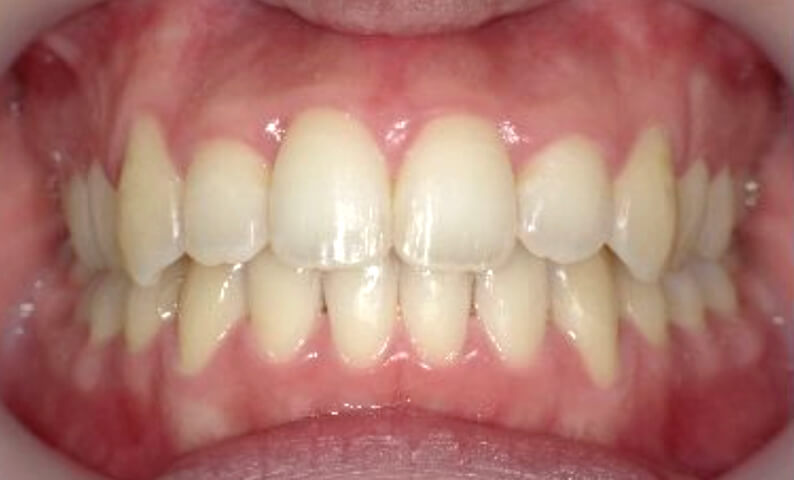

症例_025 上下顎の部分矯正

治療期間:13ヶ月金額:51万円+税女性前歯のガタガタ出っ歯

| Before | After |

|---|---|

|